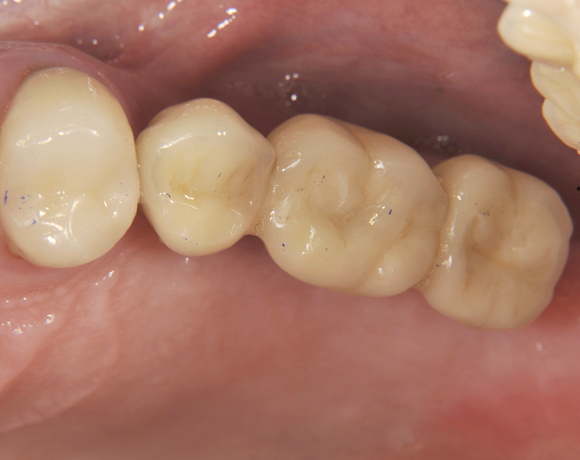

Seitenzahnbrücke auf Implantaten

Mit dem zweiteilige vollkeramische Implantat lassen sich Freiendsituationen lösen, damit lässt sich eine Prothese vermeiden.

Im vorliegenden Patientenfall wurden für die Zähne 25 und 27 jeweils ein Implantat gesetzt. Nachdem die Implantate eingeheilt waren, wurde 25 – 27 mit einer Brücke versorgt.